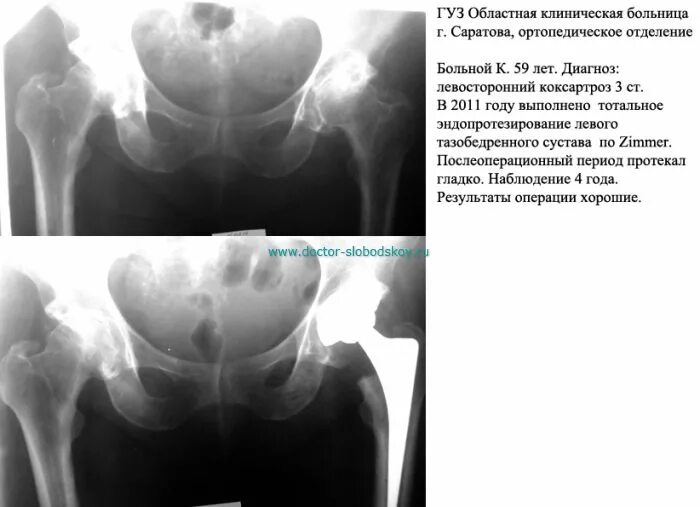

Коксартроз тазобедренного сустава код